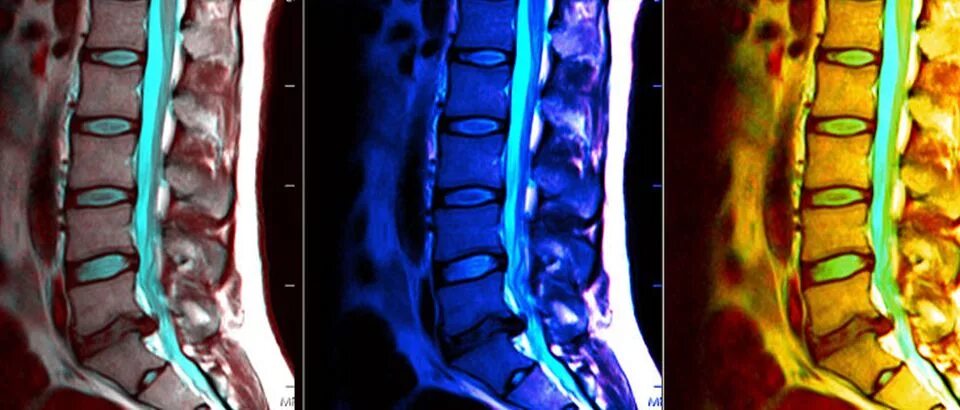

Мрт шейно поясничного отдела